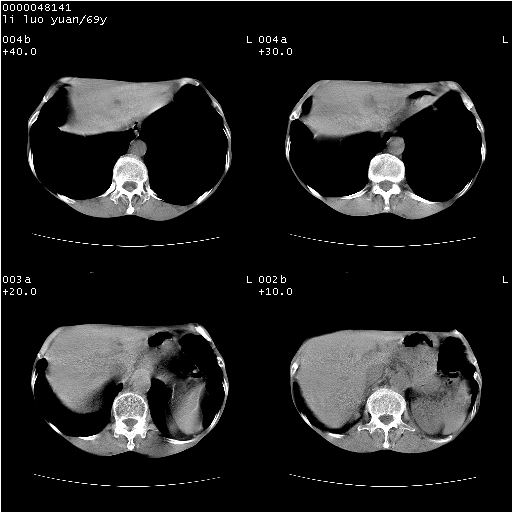

临床资料:老年患者,咯血、消瘦

影像表现:桶状胸,双肺纹理纤细、紊乱,透过度增高,肺野内可见多发、散在、大小不等的无壁高透过影,右肺中叶外侧段分叶样软组织占位,左上肺纤维索条样密度影,相应层面左侧胸腔轻度萎陷,纵隔左移。

影像诊断:1、慢支、肺气肿、双下肺野肺大泡形成

2、左上肺陈旧性肺结核

3、右肺中叶外侧段占位 考虑肺ca可能性较大、建议增强及痰检脱落细胞